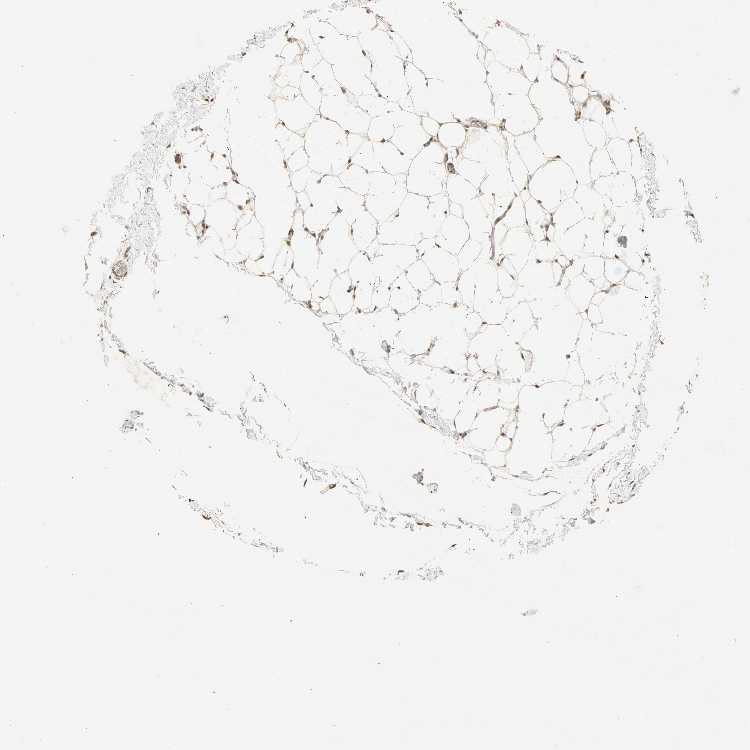

TISSUE PRIMARY DATA SOFT TISSUE Show tissue menu

SOFT TISSUE - Expression summary

SOFT TISSUE 1 - Antibody stainingi

Antibody staining in the annotated cell types in the current human tissue is reported as not detected, low, medium, or high, based on conventional immunohistochemistry profiling in selected tissues. This score is based on the combination of the staining intensity and fraction of stained cells.

Each image is clickable and will lead to virtual microscopy that enables deeper exploration of all samples and also displays staining intensity scores, fraction scores and subcellular localization as well as patient and tissue information for each sample.

Antibody HPA007124

Fibroblasts Medium